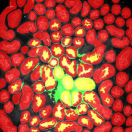

The first row in Figure 3 displays an original microscopy image (), its inhomogeneity corrected version (), and manually delineated groundtruth (), respectively. For brevity we have omitted the superscript in the notation. The second row shows segmentation results of various 3D methods such as 3D region-based active contours [10] (3Dac), 3D active contours with inhomogeneity correction [11] (3DacIC), and 3D Squassh presented in [12] (3Dsquassh). Similarly, the third row portrays various segmentation methods particularly designed for tubular structure segmentation such as ellipse fitting method presented in [15] (Ellipse Fitting), the Jelly filling method in [20] (Jelly Filling), and tubule segmentation using steerable filter [21] (Steerable Filter). Finally, the last row shows segmentation results of our proposed CNN architecture without inhomogeneity correction [27] (2DCNN) and with inhomogeneity correction (2DCNNIC).

For visual comparison we highlighted groundtruth regions in red, segmented tubule regions in green, and background in black. As observed in Figure 3, our proposed method appeared to perform better than the other six methods shown in the second and third rows by distinguishing tubules and was similar performance to 2DCNN. Note that since some methods such as Ellipse Fitting, Jelly Filling, and Steerable Filter only segmented boundaries of tubule structures, tubule interiors were filled in order to perform a fair comparison using connected components with a -neighborhood systems. Also, based on the assumption that tubule regions should contain lumen, if a filled region contained lumen pixel, the region was identified as a tubule region. However, if a filled region did not contain any lumen pixels, the region was considered as a background region.

The segmentation results shown in the second row generally missed many tubule regions. More specifically, 3Dac and 3Dsquassh could not capture the tubular structures but captured some in the center regions due to the intensity inhomogeneity of microscopy images. 3DacIC failed to segment tubular structures but captured multiple lumens inside tubules as well as some tubule boundaries. In contrast, the segmentation results displayed in the third row showed falsely detected tubules. The main reason is that these tubule segmentation methods focused only on detecting boundaries of tubular structures. In particular, due to weak/blurry edges of fluorescence microscopy images, many boundaries were not continuous causing the filling operation to overflow from one tubule to another or to the background regions. The segmentation results using the CNN generally successfully segmented and identified each tubule region.

Figure 4 provides an alternative way to show the segmentation results. In particular, yellow regions correspond to true positives which are pixel locations that are identified as tubules in both the groundtruth and segmentation results. Green regions correspond to false positives which are pixel locations that are identified as background in groundtruth but tubules in segmentation results. Similarly, red pixels correspond to false negatives, namely pixel locations identified as tubules in the groundtruth but background in segmentation results, and black pixel regions correspond to true negative that are identified as background in both groundtruth and segmentation results. The green regions indicate Type-I error (false alarm) regions and the red regions represent Type-II error (miss) regions. As observed from Figure 4, the segmentation results in the first row contained large red regions which mean large regions of tubules were missed. Conversely, the segmentation results shown in the second row contained many green regions indicating many background regions were falsely segmented as tubule regions. In contrast, the segmentation results in the third row had reasonably small green regions and red regions which indicate that the deep learning based segmentation results had higher pixel accuracy with relatively low Type-I and Type-II errors.